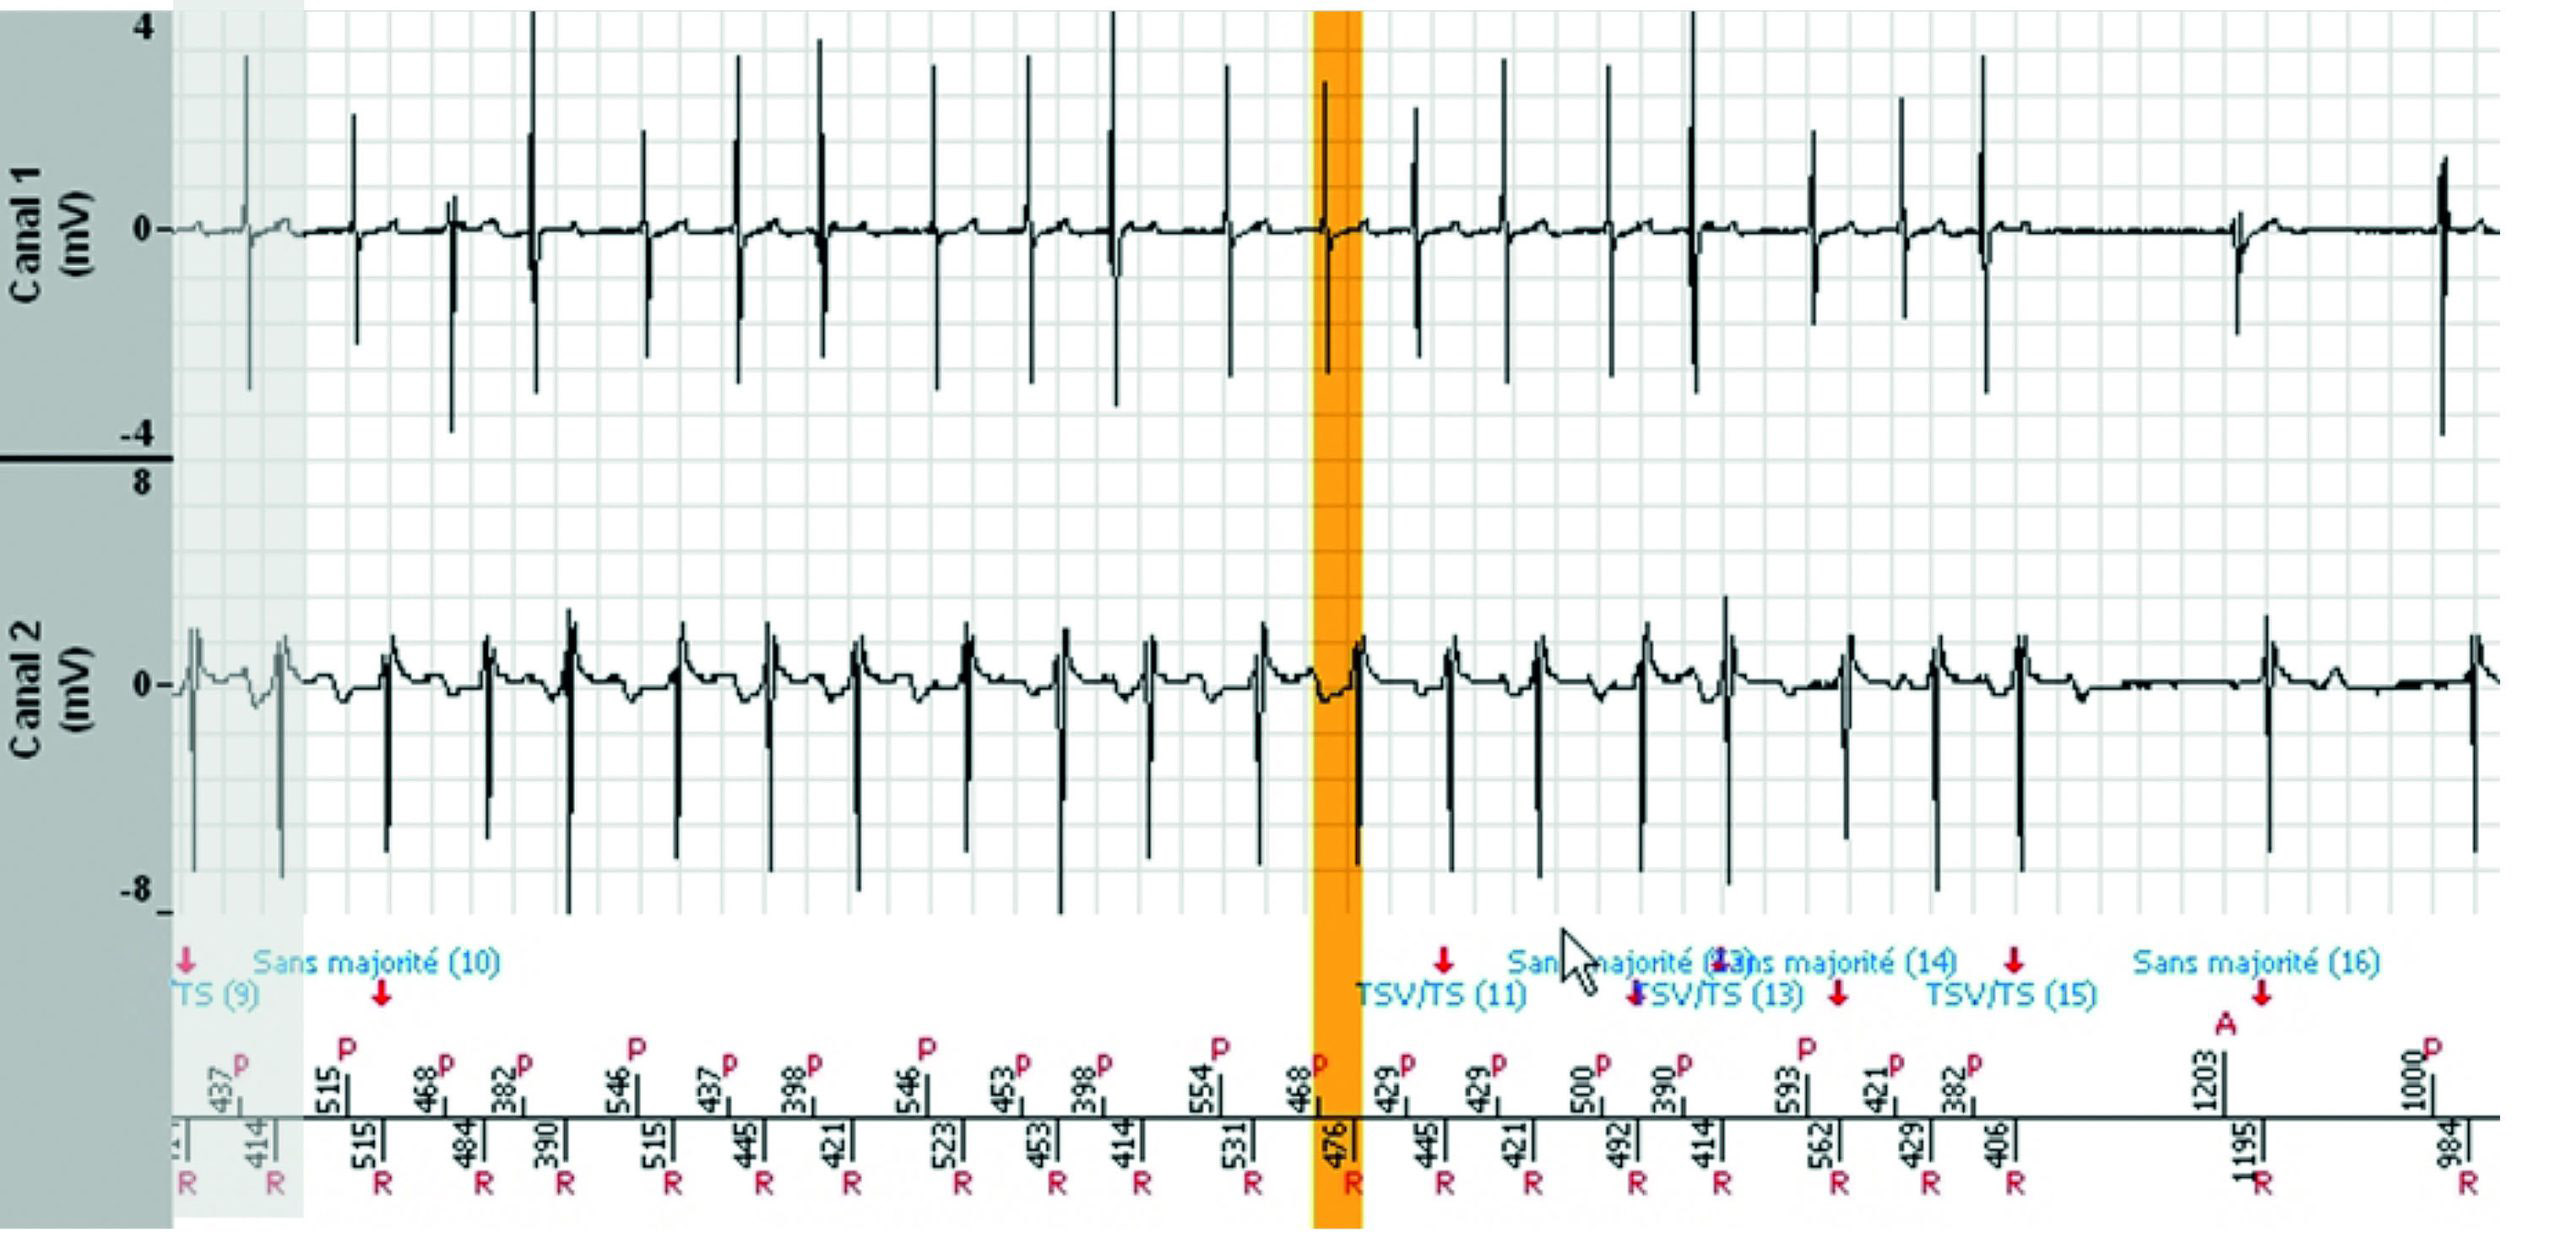

Tachogramme

EGM

Les zones ombragées sont les portions de l'EGM qui sont les répétitions de la fin de l'image précédente.

- Le tachogramme démontre des extrasystoles auriculaires et ventriculaires pendant un rythme sinusal conduit.

- La tachycardie est précédée d'un triplet ventriculaire avec une probable conduction rétrograde, suivie d'une déstabilisation immédiate du rythme auriculaire qui initie une tachycardie auriculaire instable et répercutée dans le ventricule, conduisant au diagnostic de TSV. Chaque variation de l'intervalle P'P’ induit la même variation de l'intervalle RR correspondant. La tachycardie est bien contrôlée par l'oreillette.

- Le diagnostic est non majoritaire lorsque le rythme entre ou revient dans la zone lente (non tachycardique) pendant au moins 3 cycles sur 8 (mais moins de 6), puis redevient instable avec un diagnostic de TSV jusqu'à la fin de l'épisode.

- Aucune thérapie n'a été délivrée.

- Le rythme est considéré comme stable, 1:1, avec une accélération A, d'où le diagnostic de TSV.

- A noter : les marqueurs auriculaires sont soit As soit Ar pendant tout l'épisode. Cela signifie que le défibrillateur se méfie constamment de l'arythmie auriculaire identifiée par l'algorithme de commutation de mode pour l'arythmie auriculaire qui fonctionne en parallèle. Les marqueurs As apparaissent lorsque l'intervalle Ar-As est supérieur à 500 ms. Ceci n'est pas spécifique au défibrillateur, mais à l'algorithme de commutation de mode “Fallback” de toutes les plateformes de la marque, qu'il s'agisse de stimulateurs cardiaques ou de défibrillateurs.